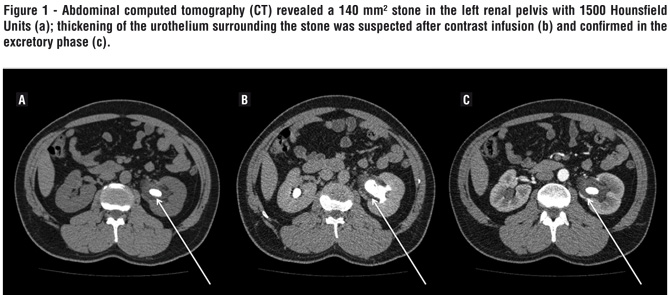

A 43 years-old man presented to our stone clinic complaining of back pain for the last 3 months. He had significant past medical history for nephrolithiasis: he had undergone unsuccessful SWL for left renal calculi five years ago and also presented with several episodes of pyelonephritis in the last months, requiring hospitalization for intravenous antibiotics. Initial laboratory work-up revealed normal serum creatinine (0.92 mg/dL) and hemoglobin levels (15.3 g/dL); urine culture was negative. Abdominal computed tomography (CT) revealed a 140 mm² stone in the left renal pelvis with 1500 Hounsfield Units (Figure-1a); thickening of the urothelium surrounding the stone was suspected after contrast infusion (Figure-1b) and confirmed in the excretory phase (Figure-1c).

Nonenhanced CT is the gold standard for detecting urinary calculi in the acute setting with reported sensitivity of 96% and specificity of 98% (1). Nearly all stones are visible on CT and secondary signs of obstruction are easily identified. Contrast-enhanced CT may be indicated if there are findings that suggest renal or other pathology which requires further evaluation (2). Our patient presented with significant edema surrounding the renal stone, fact correctly pointed-out by the radiologist reading the image exam.